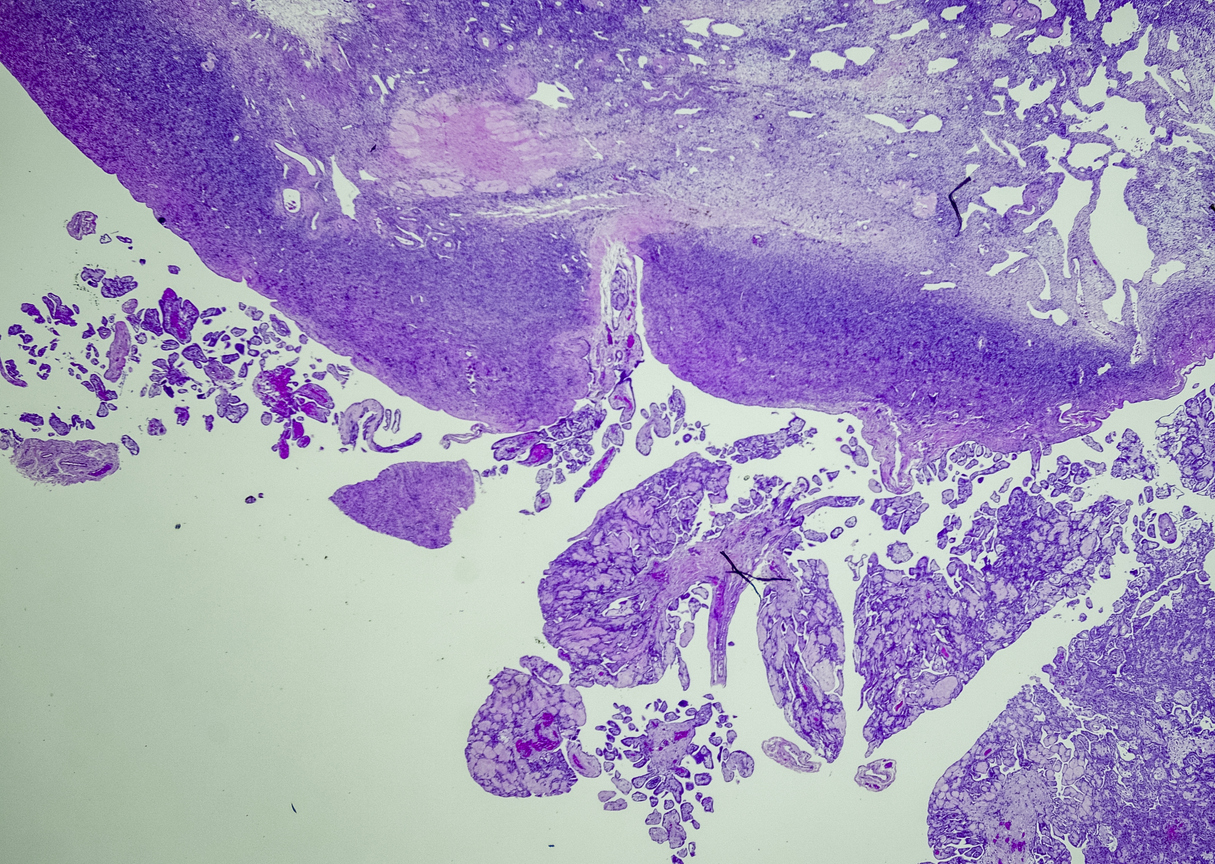

Pathologists look at tumor and tissue samples and determine what cells they can see. If the majority of cells from your mesothelioma sample are epithelioid cells, your mesothelioma subtype is determined to be epithelioid mesothelioma.

A tissue biopsy is the only way to diagnose epithelioid mesothelioma. This procedure involves taking samples of suspicious tissue. Pathologists examine the tissue samples under a microscope to identify specific cell characteristics.

Epithelioid mesothelioma cells clump together in groups and don’t tend to travel. These cell types are less likely to spread to other areas of the body. When a pathologist confirms the presence of specific cancer cells, an accurate diagnosis of your mesothelioma type can be made.

The tool or technique for studying cancer tissues is called immunohistochemistry. Pathologists look at stained samples, testing for certain proteins linked to epithelial cells. If pathologists find proteins from other cancers, they’ll rule out epithelioid mesothelioma.

The proteins that help doctors identify epithelioid mesothelioma from different types of cancer include: calretinin, D2-40, keratin 5/6, podoplanin and WT-1 protein. An official diagnosis depends on more than just immunohistochemistry. It also considers the tumor’s appearance, location and cell traits.

Epithelial subtype mesothelioma describes the type of cells the pathologist is seeing under the microscope when they look at a patient’s tumor.

While epithelioid is a subtype of mesothelioma, there are further subtypes of the epithelioid type. Pathologists can identify these cell subtypes with immunohistochemistry.